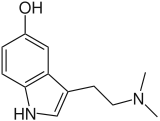

The boundary between alkaloids and other nitrogen-containing natural compounds is not clear-cut.[17] Compounds like amino acid peptides, proteins, nucleotides, nucleic acid, amines, and antibiotics are usually not called alkaloids.[2] Natural compounds containing nitrogen in the exocyclic position (mescaline, serotonin, dopamine, etc.) are usually classified as amines rather than as alkaloids.[18] Some authors, however, consider alkaloids a special case of amines.[19][20][21]

More recent classifications are based on similarity of the carbon skeleton (e.g., indole-, isoquinoline-, and pyridine-like) or biochemical precursor (ornithine, lysine, tyrosine, tryptophan, etc.).[5] However, they require compromises in borderline cases;[38] for example, nicotine contains a pyridine fragment from nicotinamide and a pyrrolidine part from ornithine[40] and therefore can be assigned to both classes.[41]

- "True alkaloids" contain nitrogen in the heterocycle and originate from amino acids.[43] Their characteristic examples are atropine, nicotine, and morphine. This group also includes some alkaloids that besides the nitrogen heterocycle contain terpene (e.g., evonine[44]) or peptide fragments (e.g. ergotamine[45]). The piperidine alkaloids coniine and coniceine may be regarded as true alkaloids (rather than pseudoalkaloids: see below)[46] although they do not originate from amino acids.[47]

- "Protoalkaloids", which contain nitrogen (but not the nitrogen heterocycle) and also originate from amino acids.[43] Examples include mescaline, adrenaline and ephedrine.